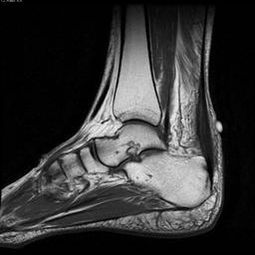

De jeito nenhum! A cirurgia é reservada para casos mais graves e que não responderam ao tratamento conservador. Na maioria das vezes, com fisioterapia e repouso, você se recupera bem.

Como saber se a dor no calcanhar é tendinite de Aquiles?

A dor na parte de trás do calcanhar, que piora com o movimento e pode apresentar inchaço, é um forte indicativo. Se a dor persistir, procure um médico para ter o diagnóstico correto.